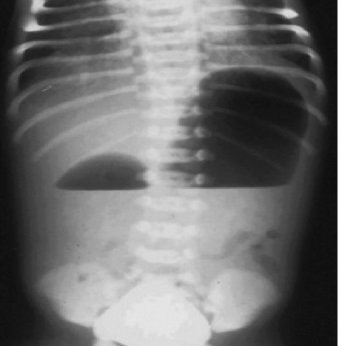

Image radiologique ASP de face d'une

occlusion duodenal neonatale , complication de

pancreas annulaire . Il y avait deux image hydro

aerique , un grande est image hydroaerique de

l'estoma et autre un peu de moindre c'est duodenum |